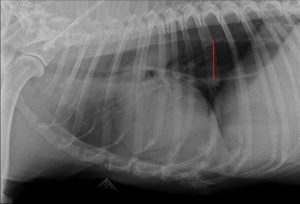

ואז קרה הבלתי יאמן! התחלנו לטפל במחלה הנדירה (מיאסטניה גרביס) והפלא ופלא סנופ החלים!!! בפעם הראשונה מזה שנה, הוא הפסיק להקיא ובצילום בית חזה שביצענו לו הוושט שלו היתה לראשונה תקינה לחלוטין.

בצילומים: סנופ (שייבדל לחיים ארוכים), צילום בית חזה בתקופת המחלה (הוושט המורחבת מסומנת באדום) וצילום בית חזה לאחר החלמה (בבית חזה תקין לא רואים את הוושט).